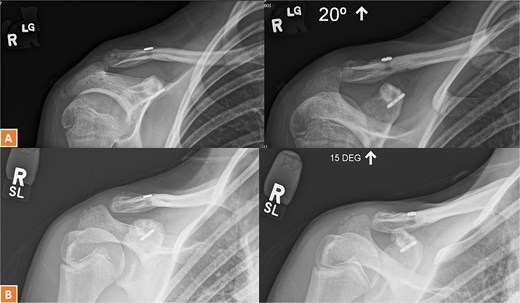

A 27-year-old male suffered a right lateral clavicle fracture after a fall (Fig. 5). He underwent TightRope fixation with stabilization of the coracoclavicular ligament. Rehabilitation was initiated early, and by three months, he had full shoulder motion and returned to overhead sports. Radiographs confirmed union, and the patient reported minor scar sensitivity and transient keloid formation, with no functional limitations (Fig. 6A–D).

Radiographs of third case showing a displaced lateral clavicle fracture with deformity.

(A, B) Radiographs showing healing of the third case and radiological union at 6 weeks and 3 months post-operatively. (C–D) Radiographs showing complete healing of the third case and union at 6 months and 12 months post-operatively.